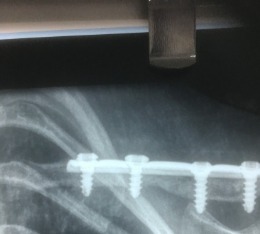

Right congenital clavicle pseudoarthrosis

A six year old girl who presented with right clavicle congenital pseudoarthrosis. Excellent functional outcome following surgical intervention.